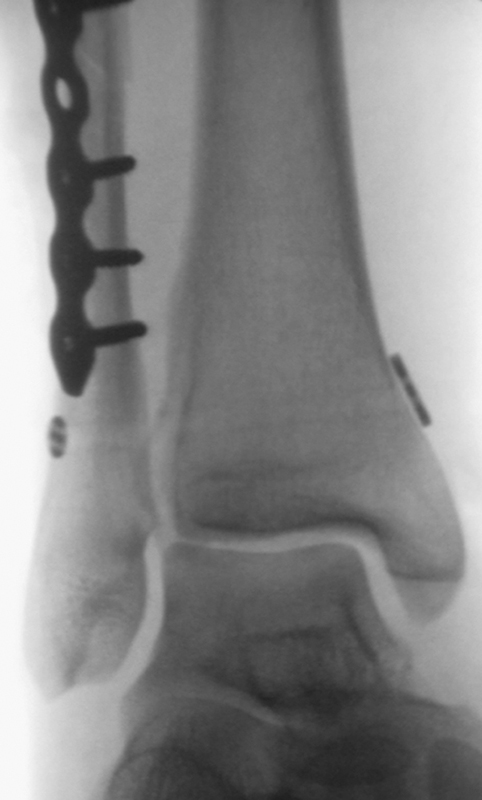

Die Versorgung von AO 44-B Frakturen erfolgt über einen längsverlaufenden lateralen Zugang. In der Regel gelingt eine suffiziente Stabilisierung mittels interfragmentärer Zugschraube (bei langem Frakturverlauf ggf. 2 Zugschrauben) und einer zusätzlichen Neutralisationsplatte (Abbildung 9 & 10).

Bei multifragmentären Frakturen (AO 44-B2.3) oder bei schlechter Knochenqualität sollte die Versorgung mittels winkelstabiler Plattenosteosynthese erwogen werden (Abbildung 11 & 12).